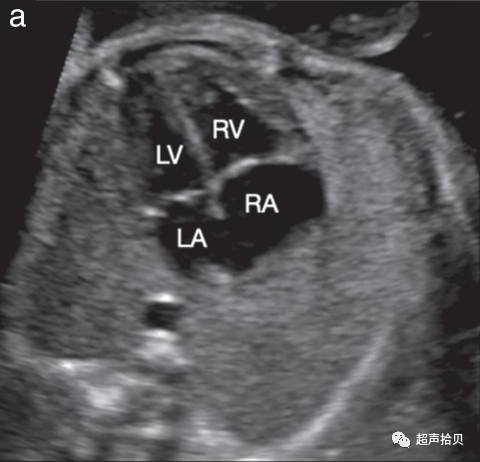

1. 在中孕期超声检查进行胎儿心脏筛查以检测先天性心脏病(图 4)。

图4 用于妊娠中期胎儿心脏筛查的代表性切面。确定心脏部位,胎儿胃和胎儿心脏在同一左侧位置(未显示)。

(a)四腔心切面 (4CV)包括两个心房,左侧和右侧(LA 和 RA),以及两个心室,左侧和右侧(LV 和 RV),并列的房室瓣和完整的室间隔。

(b)左心室流出道(b)(箭头)和右心室流出道(c)(箭头)。两条动脉流出道的大小大致相等,并且在正常胎儿中通过彼此交叉离开各自的心室。

(d)三血管切面(肺动脉(Pa)、升主动脉(Ao)和右上腔静脉(SVC))和三血管-气管切面(e)(导管弓(Da)、主动脉弓(AA)、右上腔静脉 (SVC) 和气管 (Tr)) 。

1. 胎儿心脏的超声检查从胎儿心脏四腔心切面开始。

2. 常规心脏筛查还应评估主动脉和肺动脉流出道,以检测超出仅使用四腔切面可实现的心脏畸形(图 4a)。外观正常的大血管大小大致相等,当它们离开各自的心室时应相互交叉(图 4b,c)。除了四腔切面外,对心脏流出道的常规评估提高了识别圆锥干异常的筛查性能,例如法洛四联症、大动脉转位、右心室双出口和共同动脉干畸形。

3. 三血管切面和密切相关的三血管气管切面可以改善流出道、主动脉弓和全身静脉异常的检测(图 4d、e).